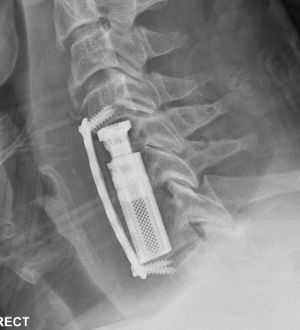

Corpectomy

Concept

Can remove body with disc above and below and decompress multiple levels

Indication

- multilevel disease

- soft and hard disc causing compression

- kyphotic deformity

Complications

Risk of graft extrusion / hardware failure - fewer points of fixation